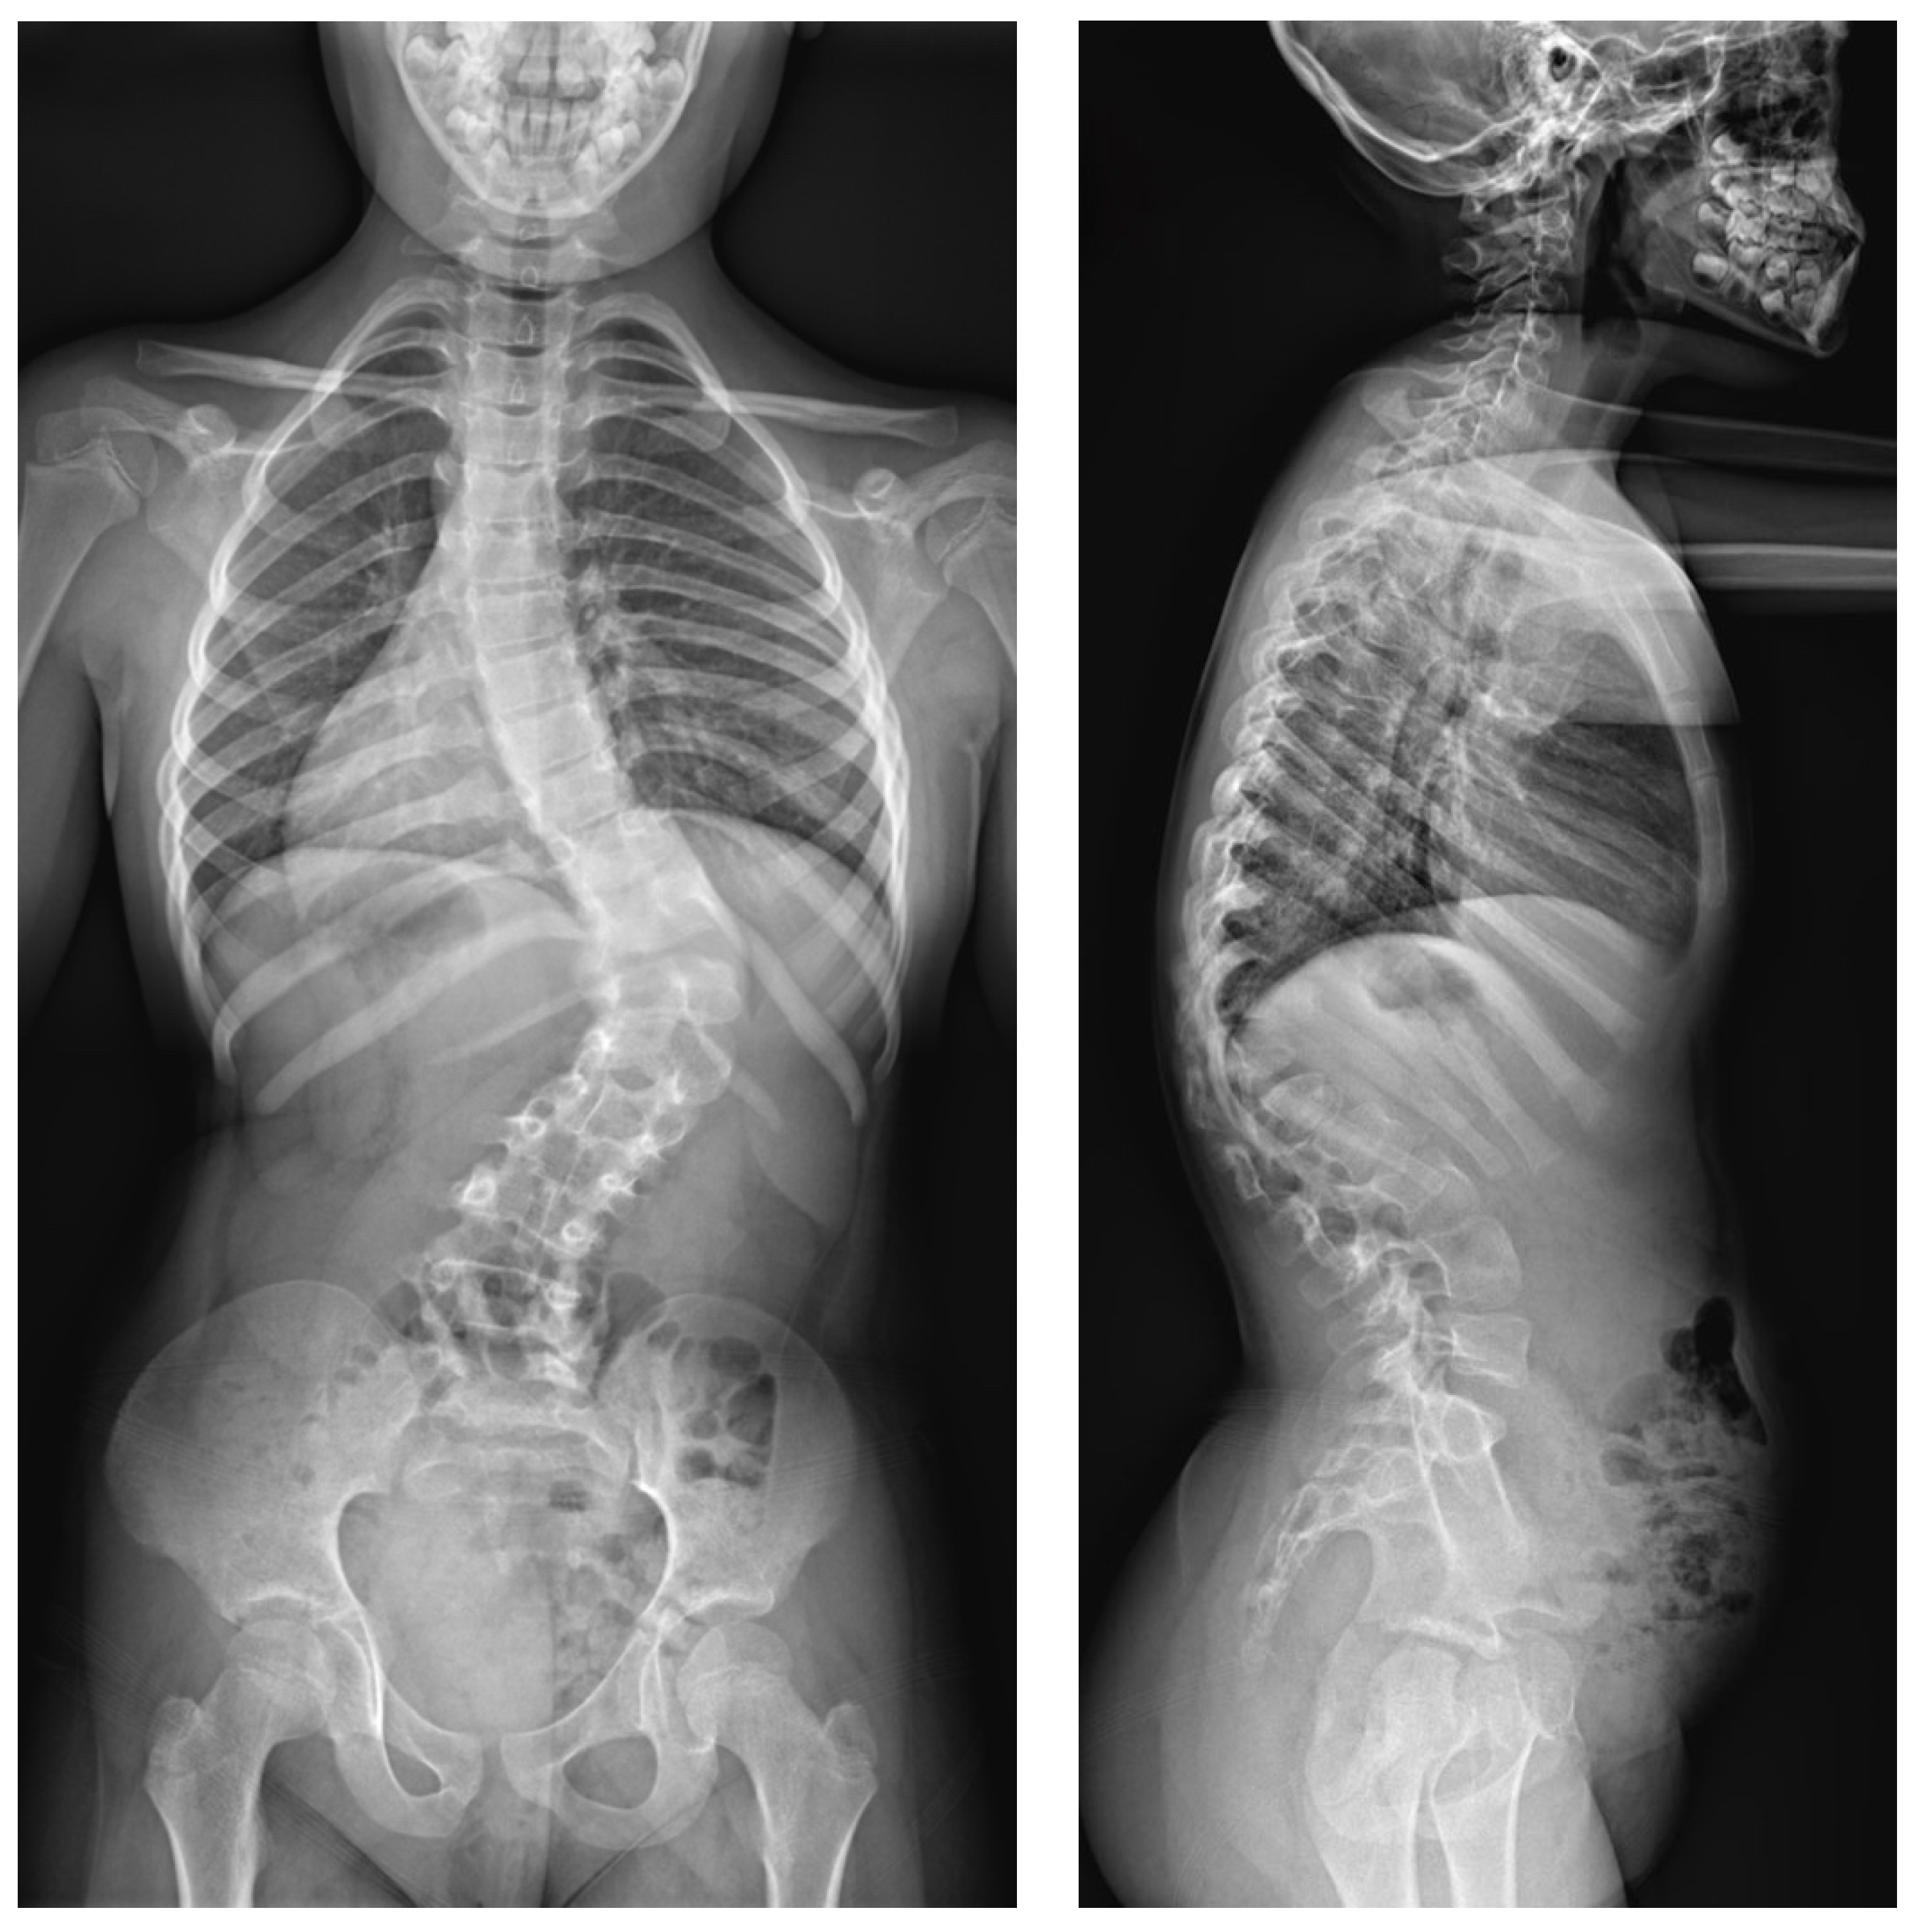

2.3. Example of Congenital Kyphosis